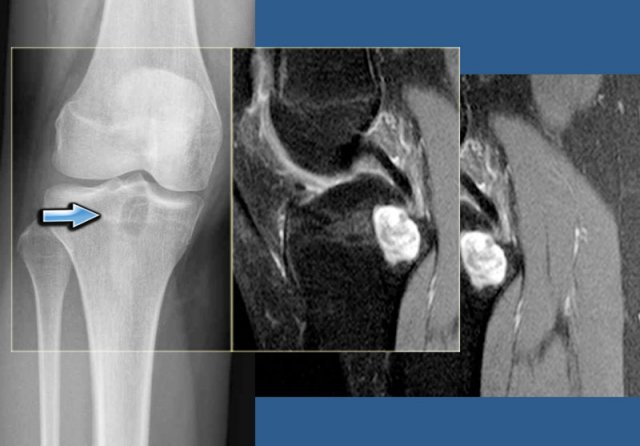

Chondroblastoma (5)

On the left an eccentric well-defined lytic lesion in the proximal femur.

CT image shows a lobulated and sclerotic border.

The location in the epiphysis is typical for a chondroblastoma.

Continue with the MR.

Same patient.

Coronal T2-WI with FS demonstrates high SI of the lesion with a low intensity sclerotic border with perilesional edema.